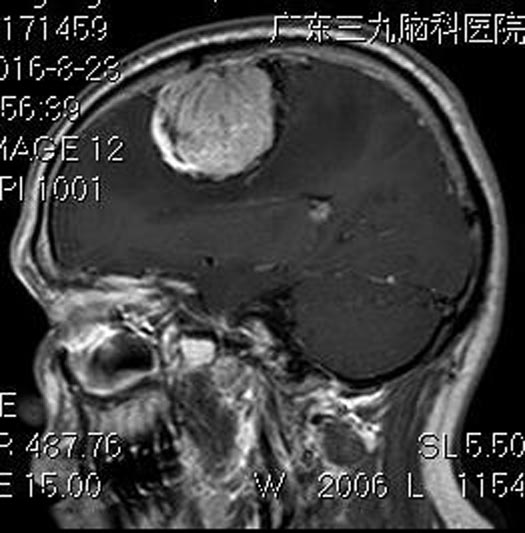

之后,头痛进行性加重,伴有左侧肢体乏力,当地医院头颅CT检查结果:右侧额部占位,考虑脑膜瘤。广东三九脑科医院头颅MR检查提示:左侧额部占位病变,大小约55.2mm×40.8mm×43.4mm,MRV示:病变区多发流空血管影,考虑脑膜瘤(血供丰富)。

由综合神经外科鲁明主任主刀,在全麻下行右额部镰窦旁脑膜瘤切除术,显微镜下见肿瘤质软、血供丰富、边界尚清,予以肿瘤全切。术后王先生头痛及左侧肢体乏力明显好转。病理结果提示:脑膜皮细胞型脑膜瘤(WHO Ⅰ级)。

▲手术前